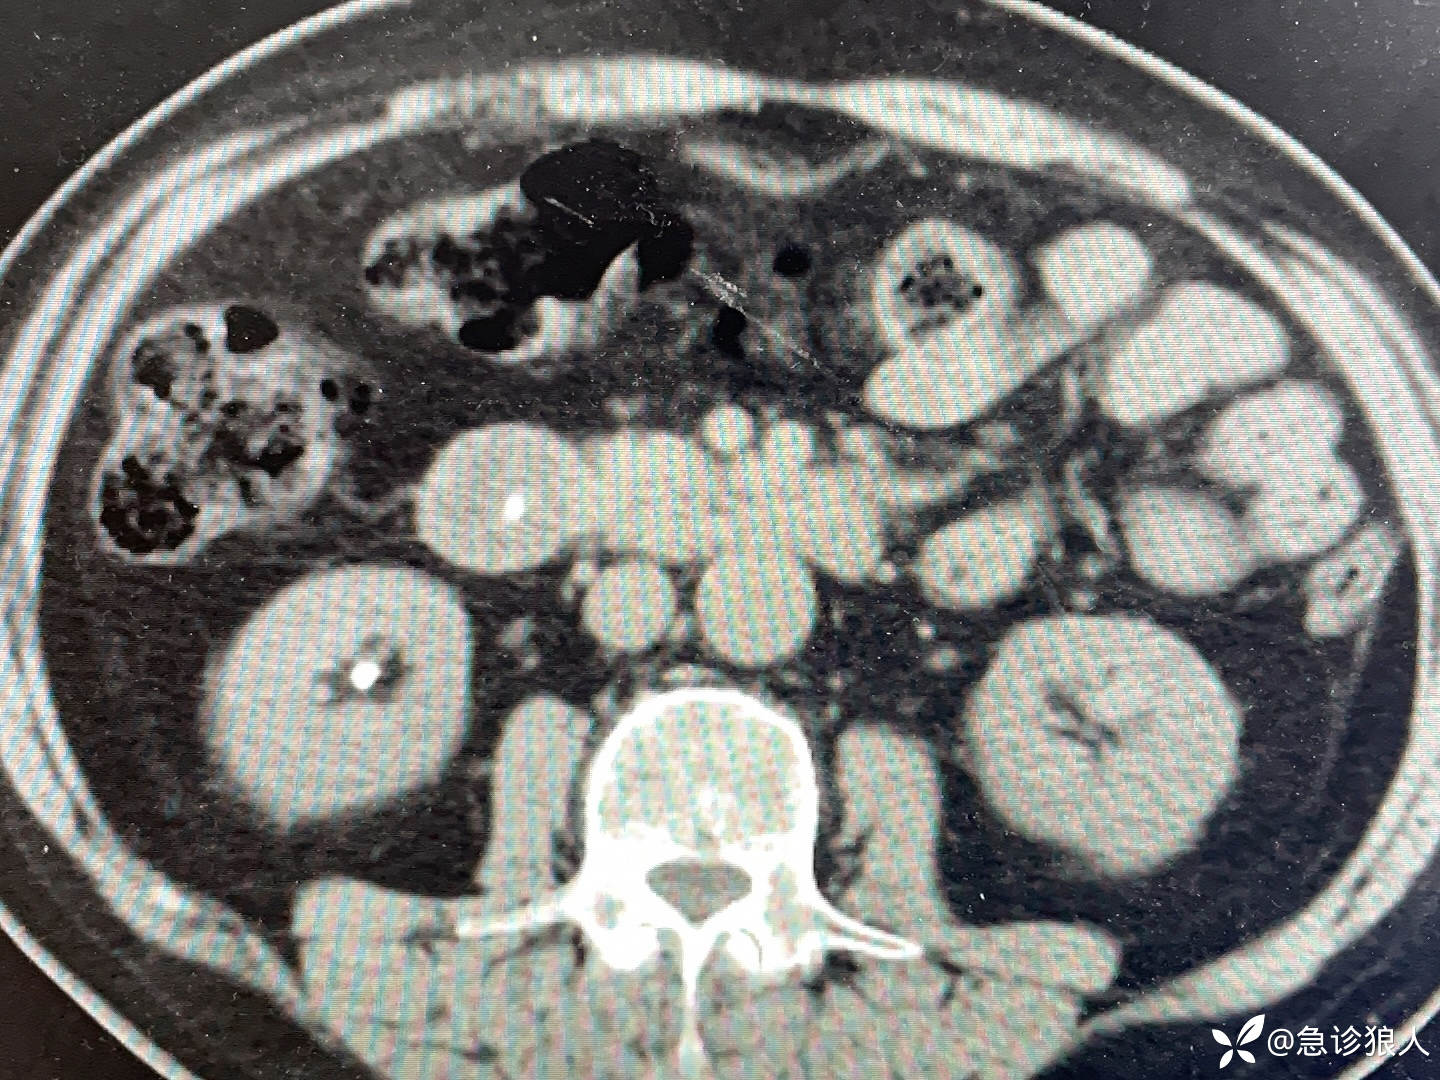

看完化验,开了个全腹CT,如下:

看完这些检查,你们感觉老人怎么了?

看完老人的CT,立刻打通影像科电话,“你看看…的CT,他淀粉酶很高,不是胰腺炎,胰腺很干净,我怀疑胆管里有石头,胆管确实稍扩张,但我没看到石头。”

影像科说,“确实不是胰腺炎,胆管确实稍微扩,我也没看到石头,要不做个超声,等等,肠腔里有个高密度的,对,石头快掉出来了,能看到十二指肠大乳头,我确定快掉出来了。”

挂断电话,我说,“你这淀粉酶1230,但不是胰腺炎,CT上胰腺很干净,我反复看你的CT,也给影像科核实了,应该是胆管里的石头快掉下来了,你在家扛了两天,需要留观,等石头完全掉下来。”